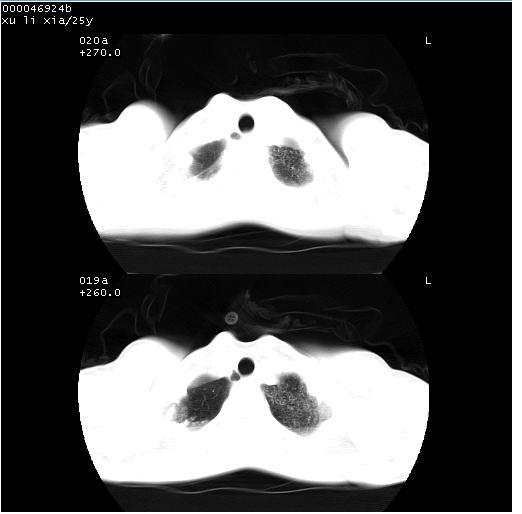

胸部ct轴位平扫(层厚10mm,螺距1.5,重建间隔10mm),图像如下:

(注:上级医院会诊胸部ct片——考虑为肺部真菌感染。)

病灶呈地图样分布于肺外围,与正常组织分界清晰+弥漫性磨玻璃影中见小叶间隔增厚呈碎石路样表现+年轻女性,无明显临床症状=肺泡蛋白沉积症?